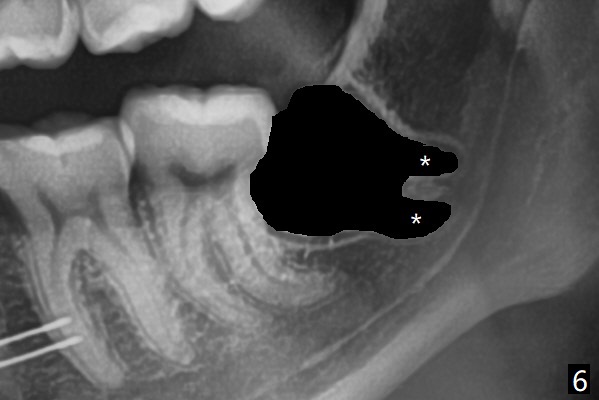

18岁女要求上大学前拔除智齿(图二),十三岁上四已经为了矫正而拔除(图一),所以现在只需要拔除下八,后者接近水平阻生,冠部可能位于下七远中颊侧(图三,四 *),所以附加切口应在七近中(红线)。智齿拔除后根部有两个牙槽窝(图五,六 *)。在右侧,塞入两个胶原塞(图七:1,2,collagen plug),其中一个末端剪开塞入根部牙槽窝。而左侧,使用一个胶原塞,但事先剪成两半(图八:1,3),第一部分也剪成燕尾,插入根部牙槽窝(1),然后在七远中放置骨水泥(1 cc Bond Apatite,2 红色),在后者上面放入胶原塞另外一半(3)。最后两侧都使用4-0 PGA 缝线。

使用胶原塞目的是预防干槽症,以前病例显示它促进骨化中心形成。骨水泥是一种医用性石膏(Biphasic Calcium Sulphate 硫酸钙 ),容易被身体吸收,3个月转换成自体骨。她哥哥(19岁)病例显示骨水泥与Osteogen Plug同样五个月会形成骨质。以后年轻人(25岁以下)智齿拔除不必植骨或者放置骨水泥。左下,右下智齿的确位于第二磨牙颊侧,事先附加切口近中,缝合后伤口不易裂开,骨粉丢失。拔除后即刻拍摄根尖片(图九,十),目的建立原有解剖,与愈合后比较,意外发现断裂牙片(F),后来取出。